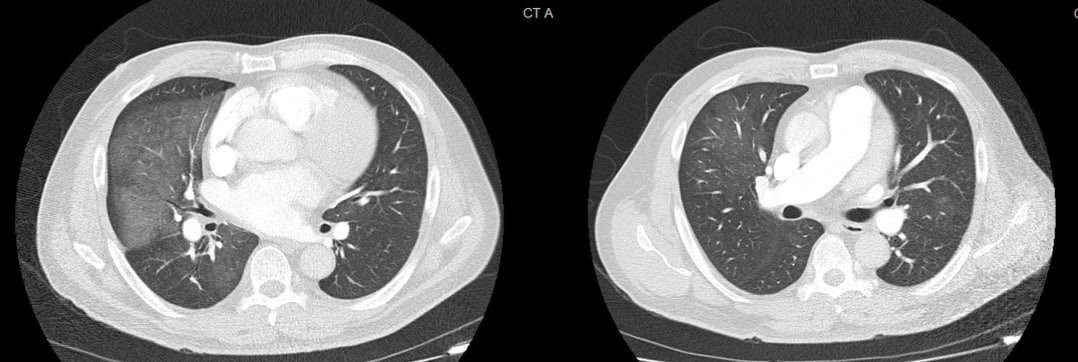

Case Description: A 58-year-old man with diabetes and poorly controlled hypertension presented with three days of hemoptysis. He denied other episodes of overt bleeding, chest pain, arthralgias, weight loss, or fever. He had a prior history of treated latent tuberculosis. He traveled to Las Vegas and noted a blow of moldy dust which he recalled as the only significant recent exposure. On arrival, BP was elevated at 206/131 mm Hg, but he was otherwise hemodynamically stable. Troponin was mildly elevated but later normalized. CBC and BMP were unremarkable. Inflammatory markers were minimally elevated (CRP: 3 mg/L, ESR: 10 mm/hr). CT chest showed diffuse bilateral ground-glass opacities. Bronchoscopy with BAL revealed friable mucosa and progressively bloody aliquots, confirming DAH. There was no evidence of malignancy or infection from BAL analysis. Extensive workup for DAH, including ANA, ANCA, cryoglobulins, anti-GBM, QuantiFERON, AFB smears and cultures, Leptospira, Legionella, Strongyloides, fungal, and bacterial cultures, was negative. TTE demonstrated normal EF and moderate LV hypertrophy; there was no valvular abnormality. With no alternate etiology, severely uncontrolled hypertension was deemed the most likely cause of DAH, supported by a few published case reports. The patient was started on nifedipine 60 mg and losartan 50 mg daily. With improved blood pressure for the remainder of his hospital stay, hemoptysis gradually resolved. At the post-hospital visit, he remained asymptomatic with good blood pressure control and complete resolution of lung opacities on imaging.

Conclusion: Severe hypertension can cause end-organ damage, affecting the heart, brain, and kidneys; however, DAH is a poorly recognized complication. Proposed mechanisms include alveolar capillary stress failure, microvascular endothelial injury, and pulmonary venous hypertension. While DAH is a rare presentation of severe hypertension with very few cases reported in the literature, our case highlights this unique complication and the importance of strict blood pressure control in its management.